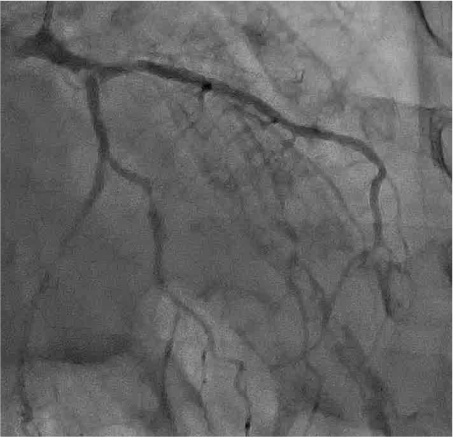

LCA CAG

-

15:20 - 16:50 Live Demonstration 4